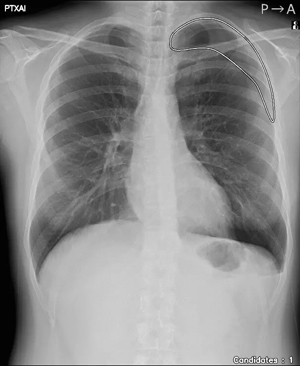

「CXR Finding-i 気胸検出タイプ」は、胸部単純X線画像をAI※2で解析することで重要所見である気胸の候補を迅速に検出し、候補領域を画像上に表示することで見落とし防止を支援する。病変検出性能を示す指標である感度※3は95%と高い水準を実現していることに加え、気胸が存在しない画像をAIが正しく陰性(気胸なし)と判断した割合を示す特異度※4は96%であり、病変を見逃さないようにしつつ偽陽性も抑制した高精度の検出性能が特長である。

気胸の診断支援を行うプログラム「CXR Finding-i 気胸検出タイプ」と連携することで、ガイドラインにおいて一般撮影で診療放射線技師が発見した場合に報告すべきSTAT画像所見の一つに挙げられている気胸の候補を高精度で検出することができる。